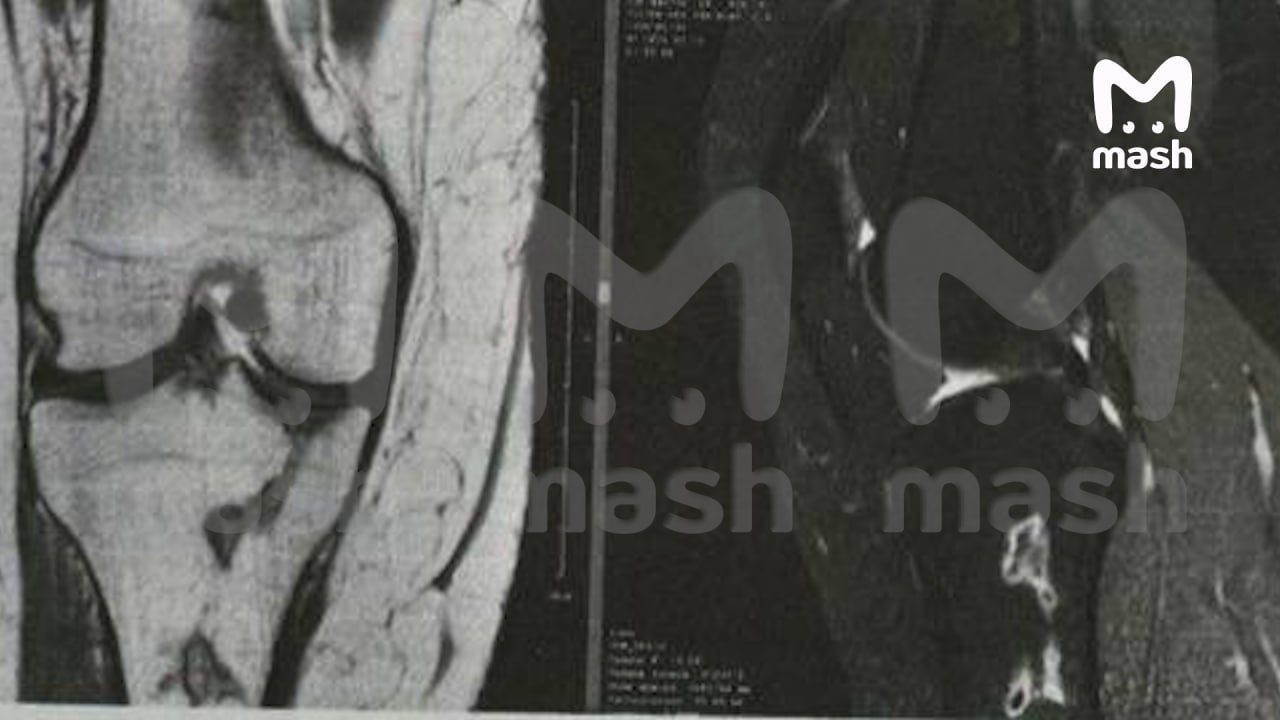

Независимая экспертиза установила, что хирург повредил кровеносные сосуды, что привело к некрозу тканей и инфаркту тазобедренной кости. Женщина подала иск в суд, требуя компенсацию в размере 4,8 млн рублей, включая затраты на лечение и моральный ущерб. Клиника, в свою очередь, обвиняет пациентку в мошенничестве, ссылаясь на подписанный ею отказ от претензий.